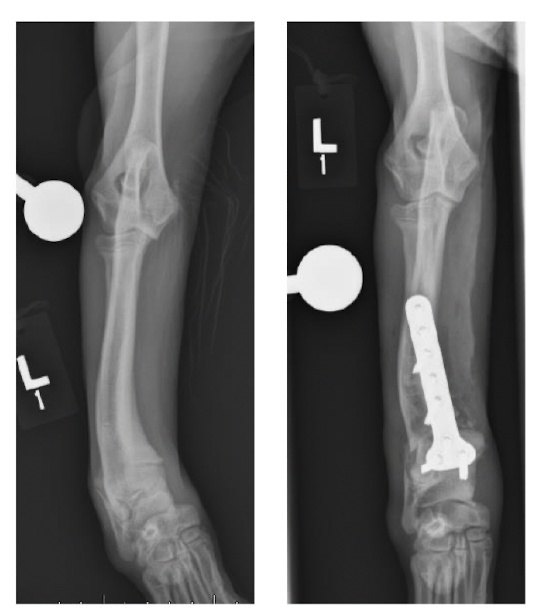

bridging plating

A

bone does not share the load

try to fix bone alignment and length, allow for secondary/indirect healing

when to use bridging plating

comminuted diaphyseal fracture (mid shaft many pieces)

mal-union/angular limb deformity- opening wedge osteotomy